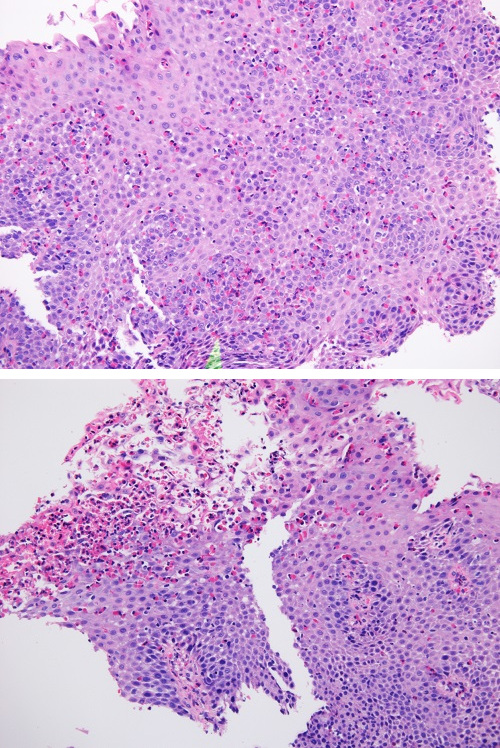

Adolescente de 15 años de edad en revisión en consultas externas de Digestivo Infantil por esofagitis eosinofílica (EEo) desde hace tres años. Clínica de debut en forma de impactación en esófago medio por un trozo de carne, que fue resuelto tras la realización de una endoscopia urgente, en la que se objetivaron estigmas macroscópicos de afectación fibroestenótica. Se documentó la presencia en los tres tercios esofágicos de infiltrado tisular eosinofílico significativo (máximo de 75 eosinófilos por campo; Figuras 1 y 2). El tratamiento con inhibidores de la bomba de protones y corticoides tópicos deglutidos resultó eficaz para atenuar las manifestaciones clínicas, pero ineficaz para revertir la inflamación, pese al buen cumplimiento terapéutico. Se desestimó el tratamiento dietético de exclusión, dada la importante reticencia del paciente a la adherencia al mismo. Se probó posteriormente con dupilumab. Se obtuvo la triple remisión: clínica, endoscópica e histológica (Figuras 3 y 4).

Figuras 1 y 2. Biopsias previas al tratamiento con dupilumab. El punteado rojizo corresponde a un infiltrado eosinofílico significativo